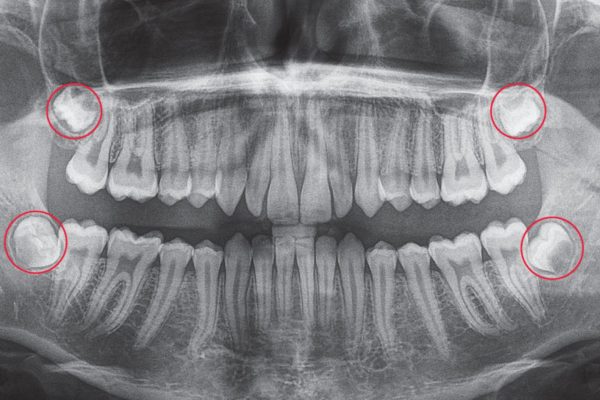

Răng khôn có mấy cái? Có phải ai cũng mọc đủ 4 chiếc răng khôn không? Răng khôn (hay còn gọi là răng hàm số 8, tiếng Anh là wisdom tooth) là những chiếc răng mọc cuối cùng trong cung hàm, ...

Mấy tuổi thì mọc răng khôn? Không mọc răng khôn có sao không? Răng khôn (còn gọi là răng hàm số 8 hay wisdom teeth) là nhóm răng mọc cuối cùng trong hàm người trưởng thành. Dù mang ...